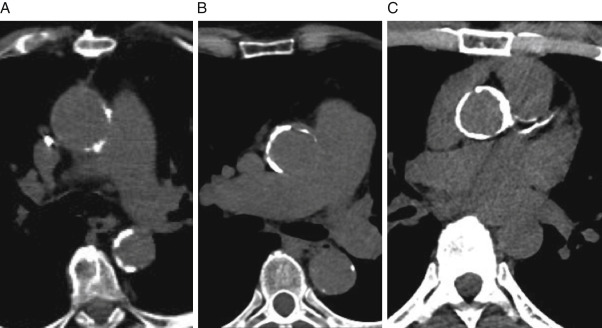

Только полюбуйтесь на эту костяную трубочку, в которую превратилась аорта.

Thoracic Aortic Calcification: Diagnostic, Prognostic, and Management Considerations